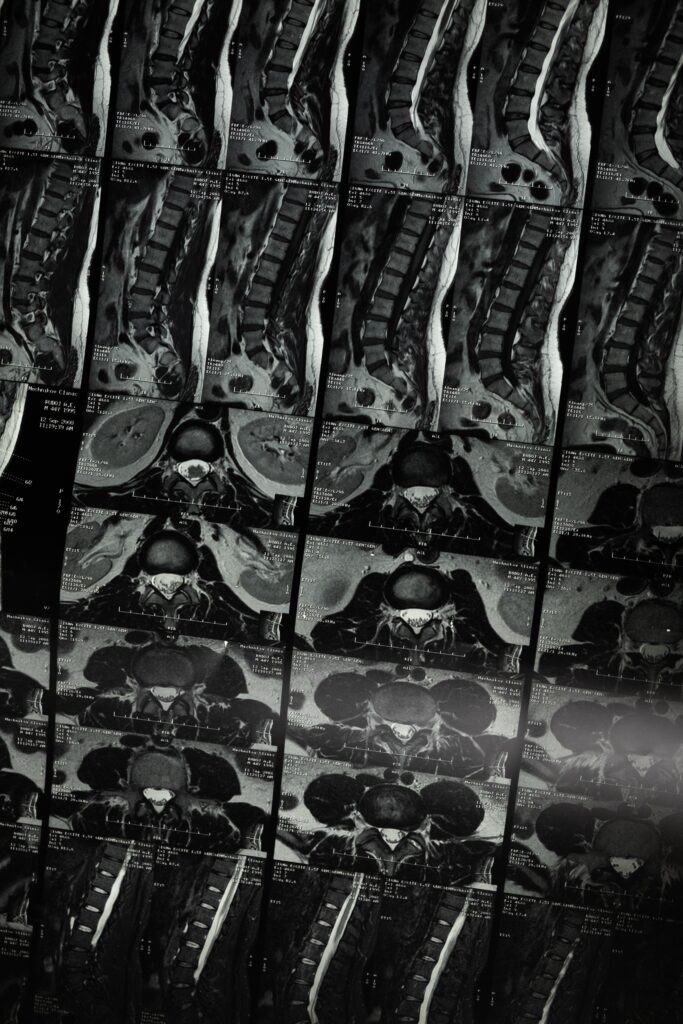

Në eksperimentin e tyre të fundit, shkencëtarët përdorën analiza të avancuara gjenetike për të identifikuar grupet e qelizave nervore jetike për ecjen pas një dëmtimi të pjesshëm të palcës kurrizore. Gjetjet e tyre të mëparshme zbuluan se rigjenerimi i aksonit përgjatë dëmtimit nuk ndihmoi në rikuperim.

Në të kundërt, kur sinjalet kimike u përdorën për të drejtuar aksonët rigjenerues drejt objektivit të tyre origjinal në palcën kurrizore lumbare, përmirësimet në aftësitë e ecjes ishin të dukshme te minjtë me lëndime të plota të palcës kurrizore.